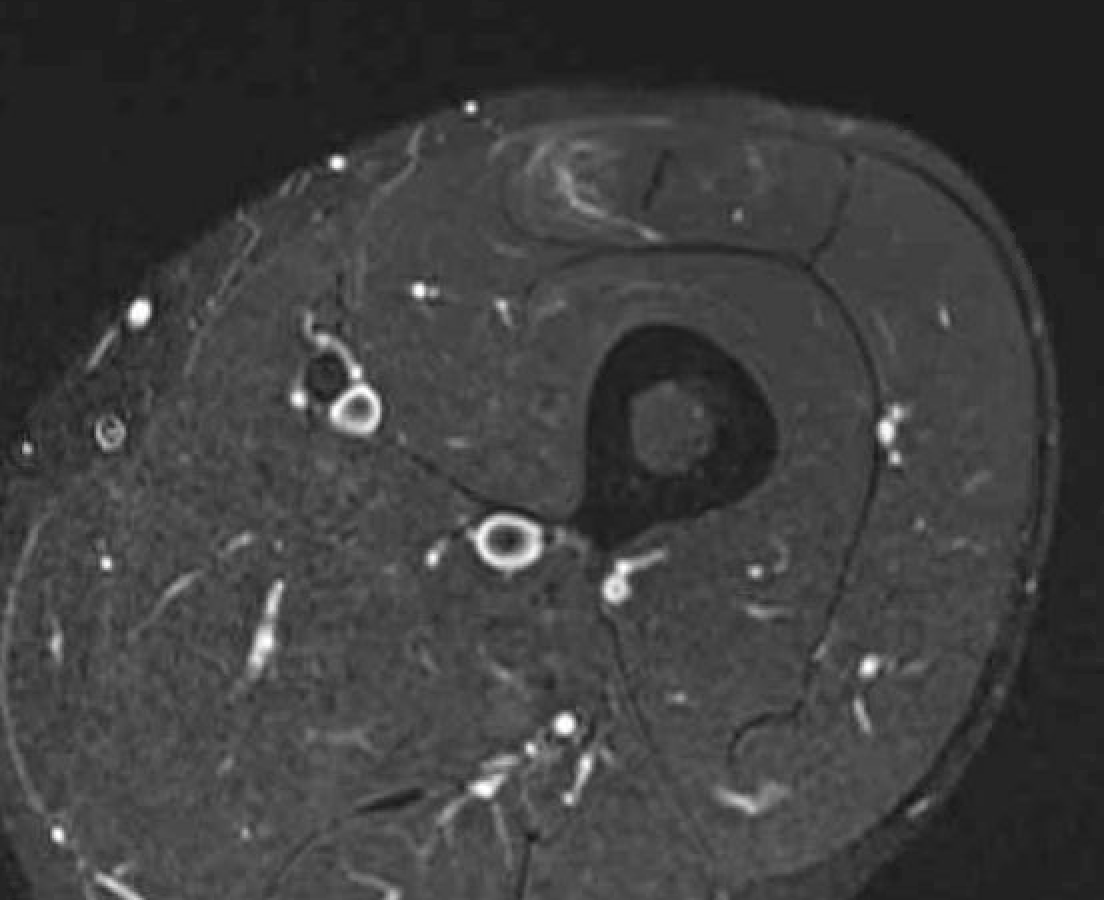

Grade 3C proximal central tendon rectus femoris

Grade 4C direct head MTPJ rectus femoris